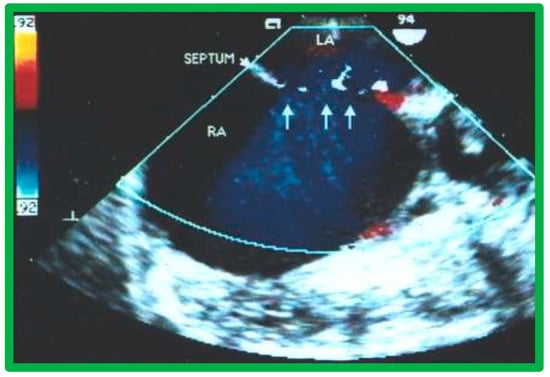

2. Diagnosis

9. Follow-Up after Device Occlusion

9.4. Residual Shunts